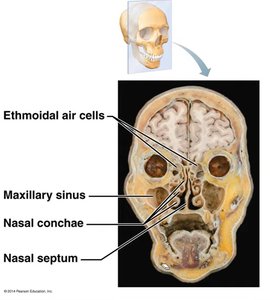

Nasal Cavity and Paranasal Sinuses

The nasal cavity provides an airway, moistens and warms air, filters particles, resonates sound for speech, and houses olfactory receptors. The paranasal sinuses open into the nasal cavity and are lined by respiratory mucosa, performing similar functions.

Turbinate Bones (Conchae): Increase surface area for warming and humidifying air.

Mucosa: Contains olfactory (smell) and respiratory (filter, heat, moisten) regions.